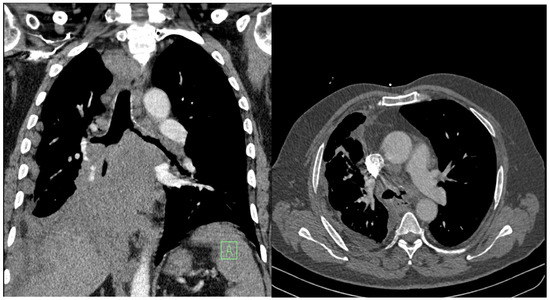

Clinically, exertional dyspnea dominated, which had worsened over the previous few days, as well as a cough, general weakness, fatigue, and a loss of appetite. In the physical examination, the patient had an oxygen saturation on pulse oximetry of 88%, was normotensive, without tachycardia, and had a BMI of 32 kg·m−2. His breathing was weakened basally on both sides, without secondary phenomena. The laboratory examination excluded inflammatory etiology. Complementary CT-angio scanning ruled out pulmonary embolism but showed the progression of a tumorous mass under the right hilum, with compression of both main bronchi and growth of the tumor into the left main bronchus (Figure 3).

Palliative rigid bronchoscopy was indicated, with the aim of re-opening the central airways. During bronchoscopy, tumorous granulations were visualized on the main carina, which completely occluded the left-sided bronchial tree. On the right side, the main bronchus and bronchus intermedius were funnel-shaped, the hilar carina was significantly widened, and the orifice of the right upper lobe bronchus was free. The area around the middle bronchus orifice was covered with fragile contact bleeding granulations, and the lumen of the lower lobe bronchus on the right was completely obliterated.

Figure 3. Progression of the central tumor on the right side of the lungs. Vascular structures and the main bronchi are involved and compressed, and the masses also extend into the left main bronchus.